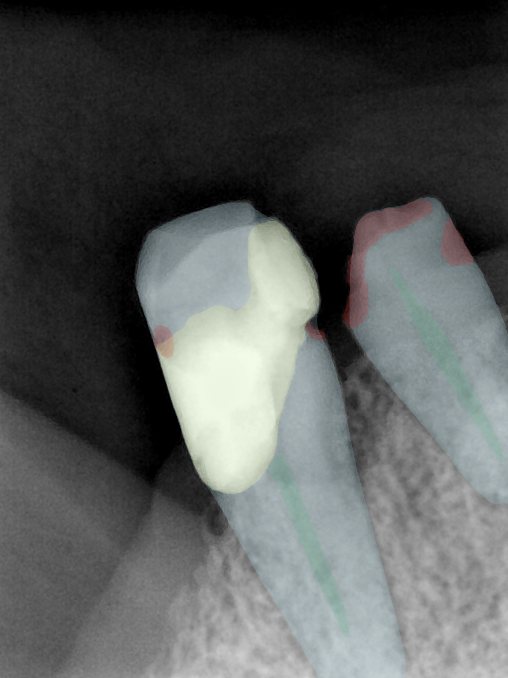

CR/DR 牙齿分割阶段记录

当前进展

- 完成了 CR/DR 牙齿相关分割训练

- 当前结果已经达到阶段预期,但仍有细节问题需要继续处理

相关测试

遇到的问题

- 训练过程中出现过 mask 下移问题

- 部分结果会出现 box 填充异常

- mask 边缘仍然有比较明显的锯齿感

参考

第二版算法问题测试